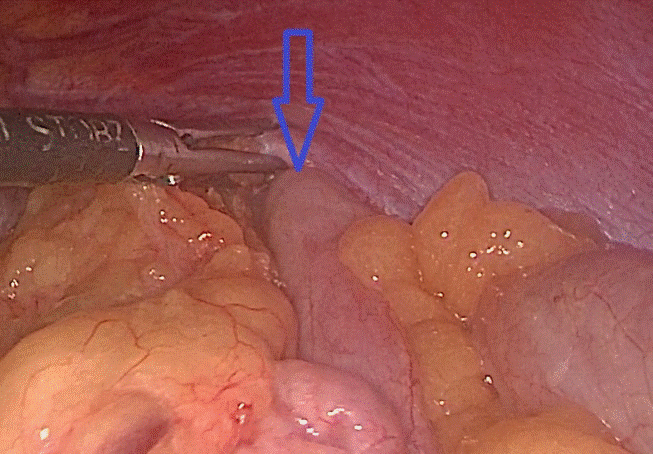

| Đại tràng chui qua lỗ thoát vị lên trên ngực trái. Ảnh: BS cung cấp |

Tại đây, bệnh nhân H. đã được chỉ định mổ nội soi để sửa tổn thương và phục hồi cơ hoành. Khi đưa máy soi vào ổ bụng, phẫu thuật viên nhận thấy gần toàn bộ đại tràng ngang, lách, dạ dày và mạc nối lớn đã chui qua cơ hoành lên khoang màng phổi bên trái. Sau khi đưa các tạng trên trở lại ổ bụng, tổn thương cơ hoành bên trái lộ rõ là một lỗ khuyết rộng khoảng 6x8 cm.

Đây chính là nguyên nhân gây ra thoát vị, kết hợp với tiền sử có chấn thương, chẩn đoán trong mổ là thoát vị hoành trái do vỡ cơ hoành. Cơ hoành vỡ đã được các phẫu thuật viên khâu phục hồi kín, ca mổ diễn ra trong 1 giờ 30 phút. Sau mổ, bệnh nhân ổn định, hết đau ngực, khó thở, chụp phim X.quang kiểm tra thấy phổi nở tốt, không còn hình ảnh thoát vị. Bệnh nhân H. được ra viện sau 6 ngày với sẹo mổ rất nhỏ của phẫu thuật nội soi.